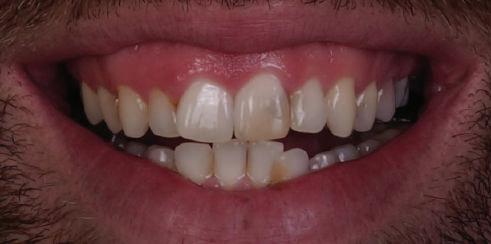

След стабилизира не на ставите и долната челюст в те рапевтична позиция постигнах орто донтски премествания и скелетни ко рекции, които обикновено са възмож ни единствено посредством ортогнат на хирургия. Преминах от аналогов мо дел на работа към изцяло дигитален, за да се хармонизира лицевата естетика чрез Digital Smile Design, като същевре менно обаче изработих функционален аналогов восъчен моделаж и на двете че люсти, за да мога да приложа оклузална та концепция на Славичек. След което напаснах препарациите с аналоговия во съчен моделаж при изцяло дигитални ус ловия с цел фрезоване на короните. Всич ки тези комбинации правят случая из ключително комплексен. В крайна сметка този сложен случай бе лекуван с най-добрата възможна ком бинация от възможности, които ана логовият и дигиталният свят предла гат, за да се постигне красота, която е следствие от отлична функция. ОКЛУЗАЛЕН „БАЛЕТ“ С РОЗОВАТА ЕСТЕТИКА Клиничен случай, победител в категория „Комплексно естетично възстановяване“ в конкурса „Усмивка на годината 2022“ Преди След

7Dental Tribune Bulgarian Edition / октомври 2022 г. Преди лечението Фиг. 1 Фиг. 4 Фиг. 7 Фиг. 10 Фиг. 13 Фиг. 16 Фиг. 17 Фиг. 18 Фиг. 19 Фиг. 20 Фиг. 11 Фиг. 14 Фиг. 12 Фиг. 15 Фиг. 8 Фиг. 9 Фиг. 5 Фиг. 6 Фиг. 2 Фиг. 3

9Dental Tribune Bulgarian Edition / октомври 2022 г. След лечението За авторите: Д-р Манол Ивчев е създател на COLDY DENT Functional Atelier, завършва дентална медицина във ФДМ, София. Шест години е стажант в ортодонтска практика. Интересите му са изцяло насочени към функционалната дентална медицина. Посещава курсовете на Доусън и Льо Гал. Преминава редица обучения, акредитирани от Института на Славичек във Виена – VieSID. Впоследствие става най-младият инструктор във VieSID. Придобива права да преподава философията на проф. Рудолф Славичек в България. В практиката си се придържа към протоколите на Славичек за функционално лече ние и диагностика, тъй като те са насочени към комплексно лечение. Завършва всички нива за морфология на зъбите и моделаж при Janos Mako. Повишава знанията си по функционална ортодонтия чрез индивидуален курс в Румъния. Д-р Ивчев е и сертифициран зъболекар по лингвална ортодонтия от Катедрата по ортодонтия от Университета по стоматология в Тегу, Южна Корея. Сертифициран е и за лечение на ортодонтски аномалии чрез миофункционални апарати, а също и за ортодонтия, подпомагана от миниимпланти, отново от Университета по стоматология в Южна Корея. Завършва индивидуално обучение по функционална ортодонтия в Университета по дентална медицина в Богота, Колумбия, както и индивидуално обучение по функционална ортодонтия и физиотерапия по про токола на Mariano Rocabado. Има завършено индивидуално обучение по функционална зъботехника и функционален Wax-Up клас I,II и III. Завършва курс за Digital Smile Design и Skin Concept в Люксембург при Christian Coachman, Florin Cofar, Paulo Kano, Josef Kunkela, Livio Yoshinagа. Зт. Leandro Gambogi, Бразилия, завършва зъботехника през 1999 г. Експерт и пионер в дигиталната диагностика. Лектор и инструктор на курсове в областта на дигиталното протезиране. Понастоящем е главен изпълнителен директор и зъботехник в DENTALE DIGITAL LAB. В периода януари 2005 г. – декември 2006 г. завършва бизнес управление и администрация в Methodist University Center Izabela Hendrix. Съавтор на книгата Odontologia Digital: Desafiando os Limites, глава 5: „Дигитално включване във времето. Технология CAD/CAM“. Преминал множество обучения при световноизвестни кли ницисти. Фиг. 51 Фиг. 54 Фиг. 57 Фиг. 58 Фиг. 63 Фиг. 64 Фиг. 65 Фиг. 59 Фиг. 61 Фиг. 62 Фиг. 60 Фиг. 55 Фиг. 56 Фиг. 52 Фиг. 53 Фиг. 66